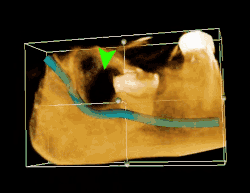

| 3D CT of an impacted wisdom tooth adjacent the inferior alveolar nerve prior to removal of wisdom tooth | |

Long-term complications can include periodontal complications such as bone loss on the second molar following wisdom teeth removal. Bone loss as a complication after wisdom teeth removal is uncommon in the young but present in 43% of those of 25 years of age or older.[23] Injury to the inferior alveolar nerve resulting in numbness or partial numbness of the lower lip and chin has reported rates that vary widely from 0.04% to 5%.[23] The largest study is from a survey of 535 oral and maxillofacial surgeons in California, where a rate of 1:2,500 was reported.[26]

Coronectomy

Coronectomy is a procedure where the crown of the impacted wisdom tooth is removed, but the roots are intentionally left in place. It is indicated when there is no disease of the dental pulp or infection around the crown of the tooth, and there is a high risk of inferior alveolar nerve injury.[32]